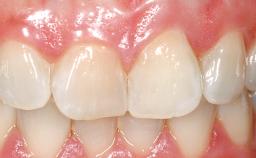

A 30-year-old female patient had lost tooth 21 and was referred to our clinic for consultation and treatment. Due to advanced apical infection, tooth 21 had been extracted two months earlier at another clinic and an acrylic-resin tooth had been bonded to the adjacent teeth. The patient desired implant treatment to avoid any damage to the adjacent natural teeth. While the patient had no history of any systemic disorder, she was a heavy smoker and exhibited medium to advanced periodontitis in the entire jaw. After the initial treatment to achieve a pocket probing depth of less than 4 mm and no bleeding on probing, a decrease in the height of the papillae mesial and distal to the extraction site and overall gingival recession were observed.